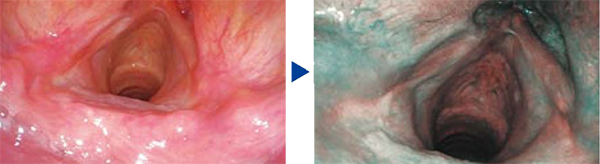

NBI(Narrow Band [maging)

NBl is an optcal imaging techndegy thatonhances the vistlty of vessels and otherstructures on or rear the mucess surlace.Thagastrointestnel tract is malrly composodl ofbocd vessels and muccsa; rarrowy bardirmagira. wrich is strenaly ascrted tyhercglobin and peretrates orly the surtace oftissues,is idgall for enhancing tre contrastbetween the two,As a resul, under rarrewv bardimaging. caparieson te mucoselsurface are disnayodin brcwun and weins intne submucosa aredisnlyed in cyan onthe mcnitor.

During endoscopic observation, NBI enhances visualizationof the capillary network and mucosal morphology.

White Light NBI